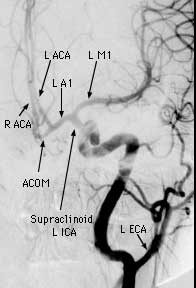

Findings: RCC angio shows the ICA follows an aberrent course, dipping inferiorly then laterally with no right A1 segment. A lobulated aneurysm involves the right MCA bifurcation. A second smaller aneurysm is present at the origin of the anterior temporal branch off the distal M1 segment. The normal left CC angiogram is shown for comparison.